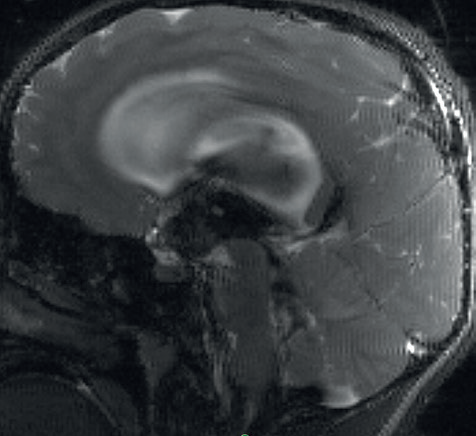

V naší kazuistice hraje ústřední roli patnáctiletá dívka, která byla sledována dětskou neuroložkou pro měsíce trvající silné bolesti hlavy. Tyto byly lokalizovány do oboustranných spánkových oblastí bez návaznosti na specifické činnosti, polohu či jiné faktory. Bolesti byly přítomny denně, dívka často vynechávala ve škole, kde se i beztak její prospěch horšil kvůli poruše pozornosti a paměti. Ošetřující neuroložka indikovala magnetickou rezonanci (MR) mozku, kde byla nalezena dilatace komorového systému (obr. 1). S tímto byla pacientka přijata do naší péče. V anamnéze nebyly vystopovány žádné rizikové faktory pro vznik hydrocefalu – perinatální anamnéza byla negativní, pacientka neprodělala žádný neuroinfekt či úraz hlavy. Na MR mozku byla viditelná výrazná dilatace komorového systému, zejména supratentoriálně, nicméně ani IV. komora nebyla fyziologické šíře. Dále bylo nápadné zúžení vtokové části aquaeductus mesencephali s velmi výrazným tokovým artefaktem na PSIF, tedy sekvenci určené k detekci toku likvoru (obr. 2), obraz zúžení mokovodu s hyperdynamickým tokem likvoru. To podporoval i výrazný bowing III. komory, tedy vyboulení III. komory a vyhlazování jejích výklenků, turecké sedlo však nebylo zvětšeno ani nikterak destruováno (obr. 3). Po příjmu pacientky byla provedena optická koherentní tomografie (OCT) zrakového nervu, která edém terče zrakového nervu neprokázala. Vzhledem k tomu, že se nejednalo o jasný obstrukční hydrocefalus, byla následně provedena lumbální punkce ke změření tlaku likvoru a odběru jeho vzorku k laboratorní analýze. Tlak byl v normě – 17 cm H20, v laboratorních vyšetřeních odchylka též nebyla nalezena. To znamená, že na MR mozku jsou jasné známky hydrocefalu, ale jak nález na očním pozadí, tak i lumbální punkce ukazují na normální tlak mozkomíšního moku. Vzhledem ke zmíněnému výraznému tokovému artefaktu likvoru přes aquaeductus mesencephali jsme se zaměřili na tento fenomén. Provedli jsme MR mozku metodou fázového kontrastu (Phase‑Contrast MRI, PC‑MRI), která umožňuje tokové parametry likvoru kvantifikovat. Opravdu se potvrdilo, že tok likvoru je hyperdynamický, maximální systolická rychlost byla 11,7 cm/s (obr. 4). Byla tedy vyslovena hypotéza, že se jedná o stenózu mokovodu a pacientce, a vzhledem k věku samozřejmě i rodině, byla navržena endoskopická stomie III. komory (ETV). Vzhledem k absenci mechanické obstrukce mokovodu při současně vysokých systolických rychlostech průtoku likvoru přes mokovod byla vyslovena hypotéza, že se jedná o funkční stenózu mokovodu. S přihlédnutím k věku pacientky byly ona i její rodina seznámeny s možností miniinvazivního výkonu ve smyslu endoskopické stomie III. komory (ETV). Rodina byla však k operaci rezervovaná, proto jsme nabídli tehdy novou diagnostickou metodu – miniinvazivní přímé měření intrakraniálního tlaku (ICP) čidlem s telemetrickým přenosem naměřených hodnot (Raumedic Neurovent‑P‑telâ). Hlavní výhodou této metody je možnost kontinuálního měření ICP i v domácím prostředí až po dobu 90 dnů. Implantace čidla byla provedena bez komplikace a pacientka byla edukována o způsobu monitorace ICP, zejména vedení deníku činností a bolestí hlavy. Po třítýdenním měření byla data analyzována a porovnána s deníkem. Byl nalezen jasný korelát mezi silnou cefaleou a hroty ICP až k hodnotám 30 mm Hg. Zvláště nápadné byly křivky během noci, kdy krátce po elevaci ICP byla pacientka bolestmi hlavy opakovaně vzbuzena. Po předložení výsledků této metody pacientka i rodina souhlasily s provedením ETV. Zákrok byl proveden bez komplikace, průchodnost stomie byla verifikována pooperačním vyšetřením pomocí MR mozku (obr. 5). Pooperačně se však symptomy pouze zmírnily a po pěti týdnech nastala kompletní recidiva obtíží. Byla vyslovena suspekce na okluzi stomie, nicméně kontrolní MR mozku toto nepotvrdila. Další postup mohl mít dva scénáře. První by znamenal připustit, že pacientčiny nespecifické symptomy nebyly dány porušenou likvorodynamikou a naše rozvaha byla chybná. Druhý by znamenal setrvání v našem předpokladu, že obtíže jsou spojeny s likvorodynamickými poměry, nicméně ETV nepostačovala k odvedení dostatečného objemu likvoru při jeho pulzatilním toku. Jedinou další léčebnou metodou by v tom případě bylo zavedení ventrikuloperitoneálního (VP) shuntu. Což je však další invazivní výkon, proto jsme uvažovali o další diagnostické metodě – lumbální drenáži. Jedná se ve své podstatě o simulaci zavedeného shuntu dočasnou drenáží likvoru ze spinálního subarachnoidálního prostoru. Po domluvě s pacientkou a rodinou byla lumbální drenáž zavedena a ponechána tři dny s celkovým objemem odvedeného likvoru 500 ml. Po celou dobu drenáže byla pacientka zcela bez bolestí hlavy. Test byl tedy pozitivní. Po vytažení drenáže se bolesti vrátily do dvou dnů. Nyní jsme s větší jistotou mohli indikovat zavedení VP shuntu. Protože jsme předpokládali, že nastavení ventilu shuntu nebude u takto komplexního typu hydrocefalu jednoduché, zavedli jsme typ ventilu, který umožní regulaci tlaku separátně pro horizontální a vertikální polohu těla – Miethke proGAVâ 2.0 s iniciálním nastavením 10 cm H2O a m.Blueâ s nastavením 25 cm H2O (obr. 6). Operace proběhla bez komplikace a pacientka byla propuštěna do domácího ošetřování s tím, že případné změny nastavení ventilu budou provedeny v rámci ambulantních kontrol. Při první kontrole pacientka udávala přetrvávající bolesti hlavy, proto bylo nastavení ventilu proGAVâ 2.0 pro horizontální polohu sníženo na 5 cm H2O. Při další kontrole za dva týdny pacientka popisovala kompletní vymizení původních příznaků vleže. Popisovala však symptomy předrénování, tedy výraznou cefaleu při vertikalizaci s rychlou úlevou v horizontální poloze. Proto bylo nastavení antigravitační jednotky m.Blueâ postupně zvýšeno až na maximum, tedy 40 cm H2O. Na tomto nastavení byla nalezena rovnováha mezi potřebou nízkoodporové drenáže likvoru vleže a zamezení předrénování sifonovým mechanismem vstoje. Pacientka je nyní sledována po operaci jeden rok, je zcela bez bolestí hlavy.